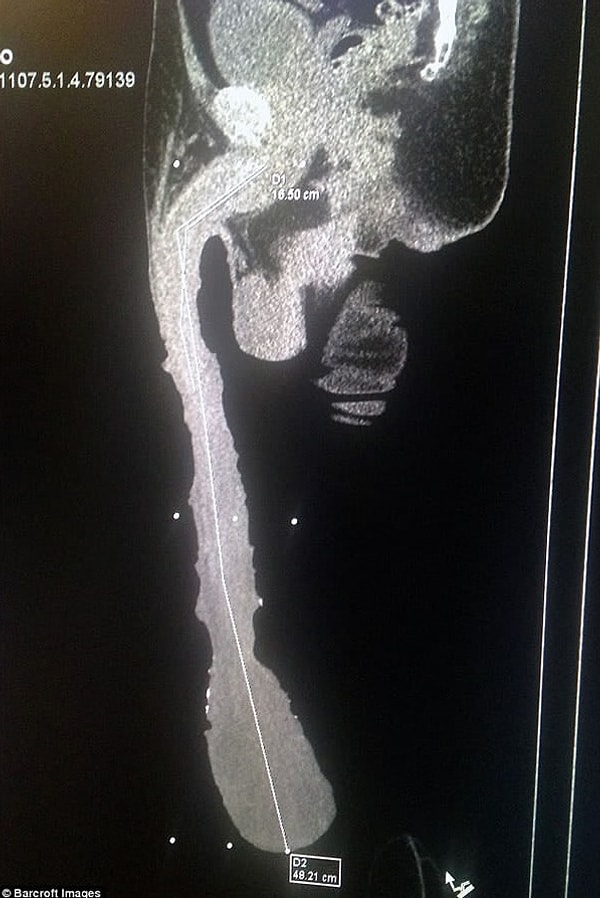

2. Длина полового члена Роберто составляет 48 см! Кабрера гордится этим, отмечая, что это достижение достойно Книги рекордов Гиннесса